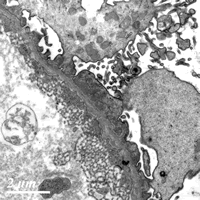

电镜下见1个肾小球(图4),节段肾小球基膜膜上见大小不一、中等电子密度的致密物,有的致密物间见基膜样物质将致密物包饶,节段基膜膜上未见电子致密物,一处内皮下亦见电子致密物。肾小球内内皮细胞胞浆连拱状,足细胞肿胀,足突广泛融合、增厚,少量微绒毛化,胞浆内见肿胀的线粒体。